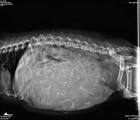

4. X-Ray

After day 55, an X-ray can give the most accurate count of how many puppies your dog is carrying. This is especially important information to have during delivery, so you’ll know when all puppies have been born.